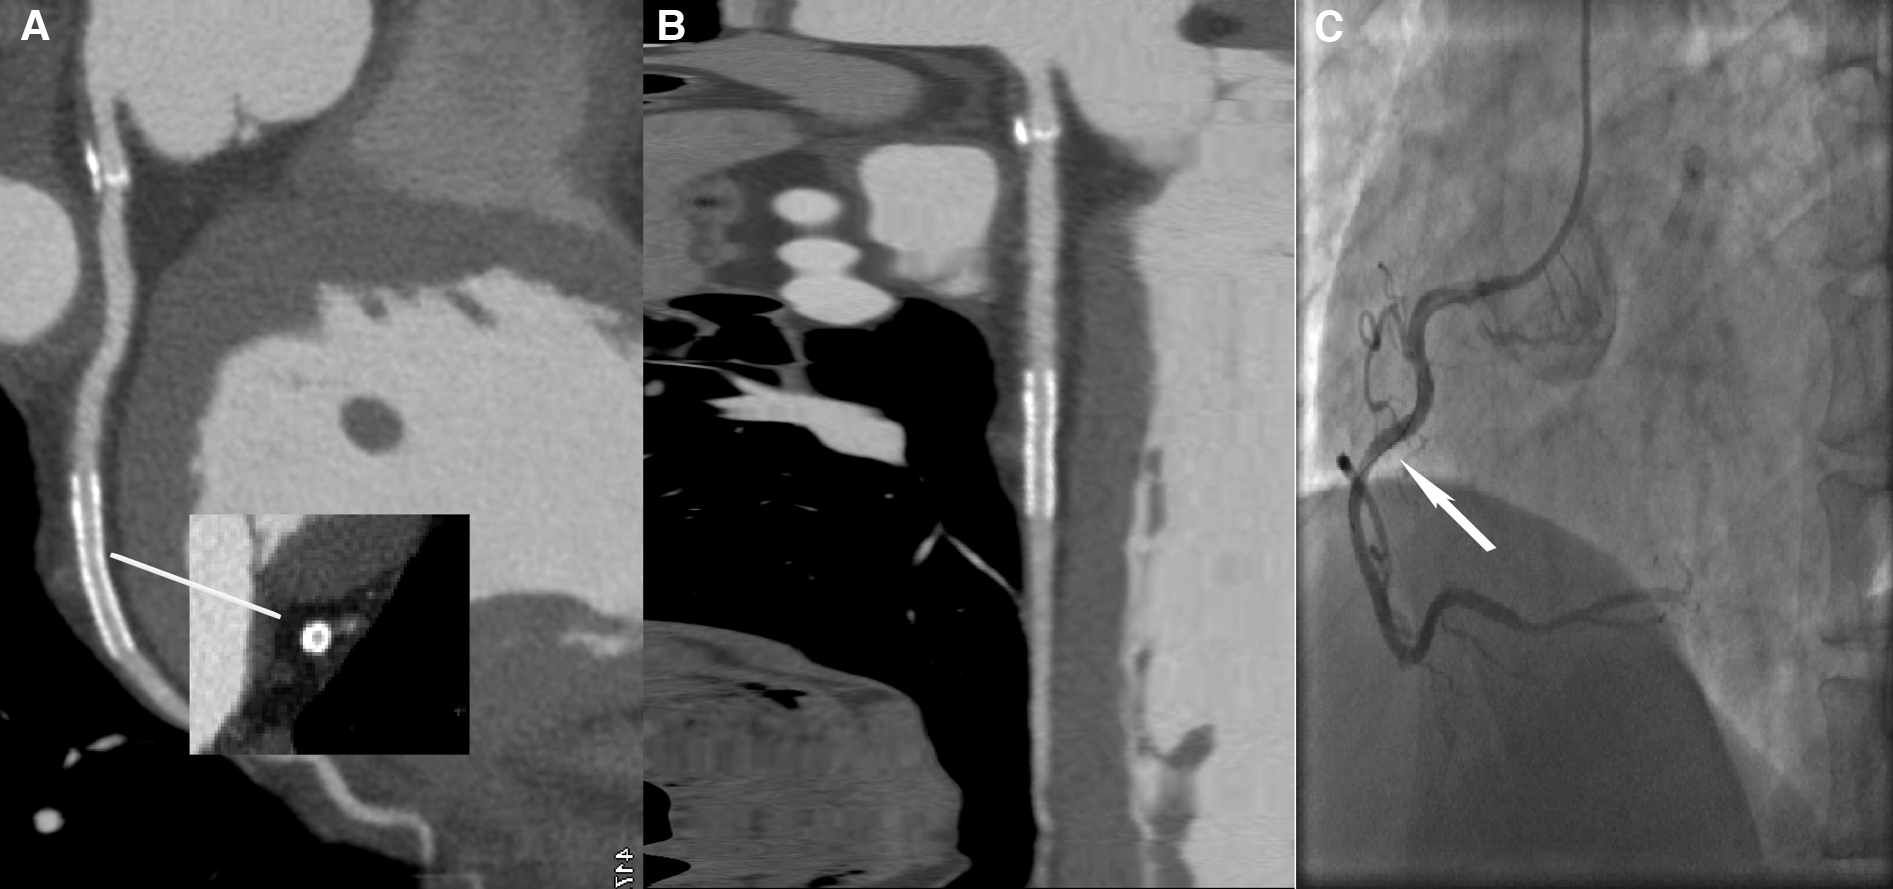

Figure 5

A 59-year-old male patient with ISR in the LD group, with a BMI of 25.56 kg/m2. (A) The image quality reached a subjective score of 5: clear stent strut definition with a clear border of the blood vessel and an image noise of 16 HU. (B) CPR image of LCX showed the absence of ISR in a 2.5 mm coronary stent (resolute, 2.5 × 22 mm, XIENCE Alpine). (C) ICA of the left circumflex confirmed the stent patency (white arrow).